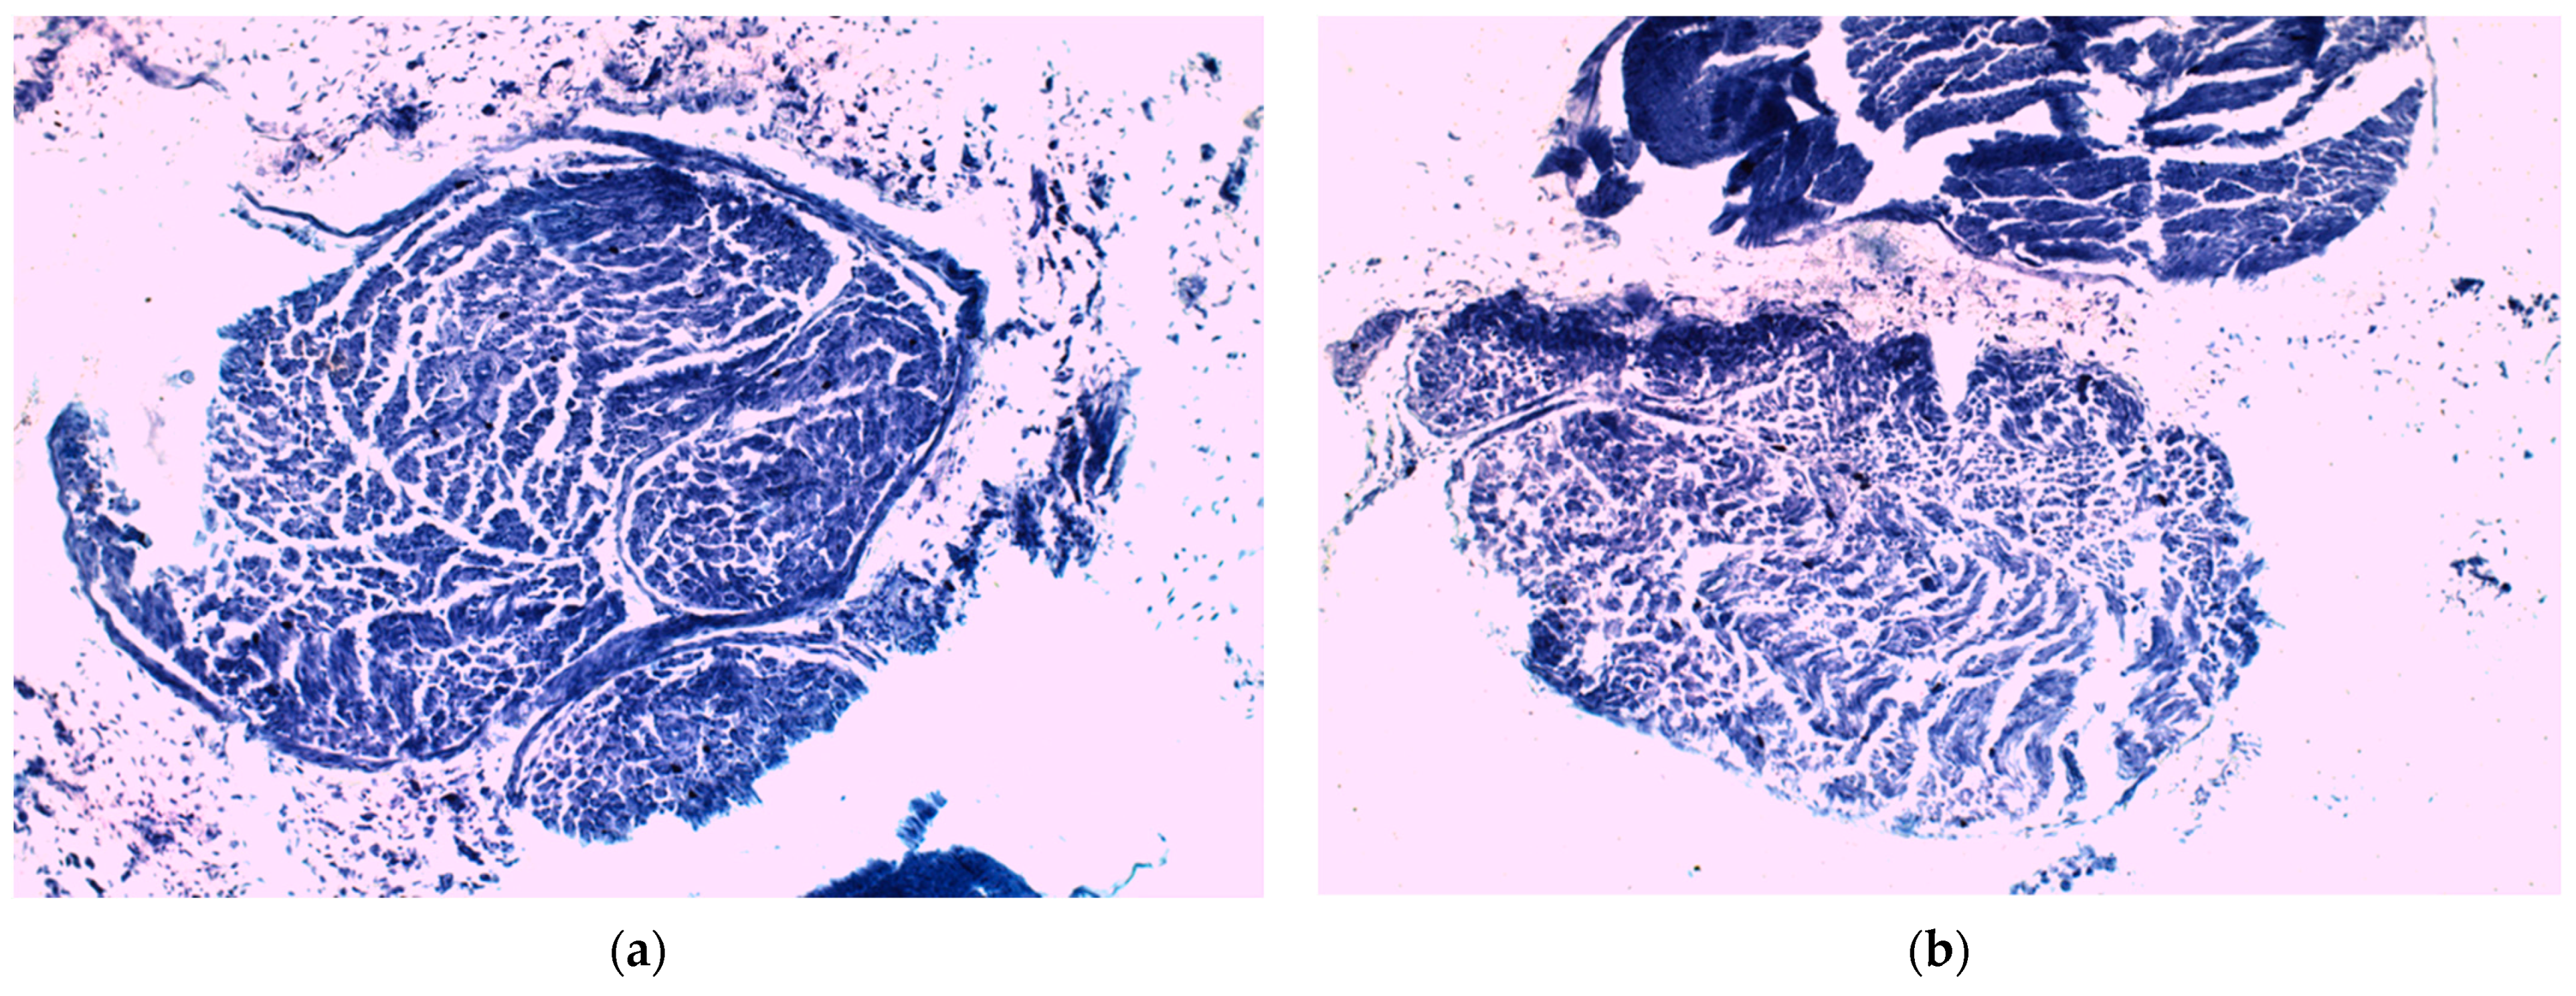

In the analysis of the right sciatic nerve samples from animals in both groups, the same differences were observed, in histological and especially in TEM analysis. Regarding the right sciatic nerve of the animals in the control group, multiple myelin sheath disorganization sites were noticed (Figure 10a and Figure 11a,b), which are in fact disorganizations of the plasmalemma extensions of Schwann cells that surround the axons. The loss of axonal myelin layers’ continuity could be described as ovoid shaped areas of rarefaction (inset of Figure 11b), which induced a degeneration of the axon into debridements that followed the original endoneural tube. These changes in the compaction of the myelin sheath could be associated with a low expression of transmembrane myelin-specific proteins that are involved in its compaction. As a result, hypomyelination or demyelination occurred and, therefore, it resulted into a poor nerve recovery. These findings correlated with what the studied revealed about the evolution of the control group from the perspective of the SFI score, pain level, and body weight.

In comparison with the control group, the right sciatic nerve of the animals that received CMNPs treatment had almost normal morphology with discrete to moderate internal disorganization (Figure 10b and Figure 11c,d). The frequency of the ovoid areas of myelin disorganization was suggestively lower than in the control group. Moreover, TEM images observed the nanoparticles mostly at the axon and myelin sheath level as small black oval shape dots.

Figure 10. Right sciatic nerve samples—histological studies. (a) Control group nerve sample; (b) CMNPs treatment group nerve sample.